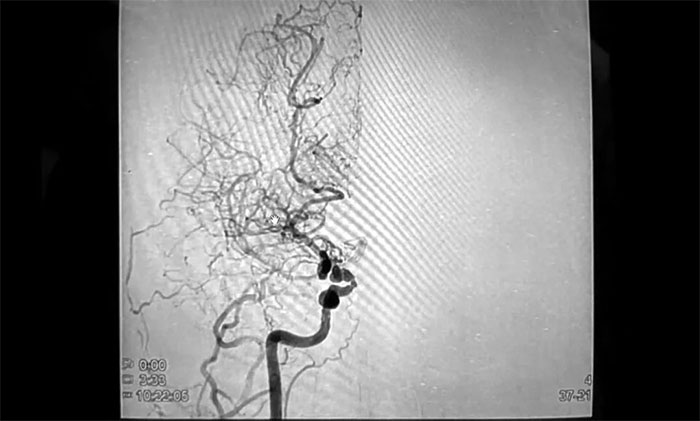

隨后,住院行數(shù)字減影血管造影(DSA)后,明確診斷為“煙霧病、顱內(nèi)多發(fā)動(dòng)脈瘤”,這著實(shí)把她嚇得不輕。

煙霧病,因顱底異常血管網(wǎng)在腦血管造影圖像上形似“煙霧”而得名,是一種病因不明的、以雙側(cè)頸內(nèi)動(dòng)脈末端及大腦前動(dòng)脈、大腦中動(dòng)脈起始部慢性進(jìn)行性狹窄或閉塞為特征,并繼發(fā)顱底異常血管網(wǎng)形成的一種腦血管疾病。

在這一迫切心理下,經(jīng)親友推薦,胡女士來到上海藍(lán)十字腦科醫(yī)院,以尋求進(jìn)一步治療。宮衛(wèi)東主任及神經(jīng)外科6A病區(qū)專家團(tuán)隊(duì)為胡女士完善了相關(guān)檢查,頭顱CTA示:右側(cè)大腦中動(dòng)脈主干節(jié)段性狹窄,中遠(yuǎn)段分支明顯減少,近乎全部閉塞;局部見代償性微細(xì)分血管網(wǎng),符合煙霧病特征。顱內(nèi)動(dòng)脈環(huán)區(qū)多發(fā)微小動(dòng)脈瘤。

▲ 右側(cè)中動(dòng)脈狹窄,異常血管網(wǎng)形成

結(jié)合其影像檢查報(bào)告,專家團(tuán)隊(duì)針對(duì)病情和治療方法展開了審慎的討論、評(píng)估。雖然胡女士目前僅有頭暈,暫無其他更嚴(yán)重癥狀,但右側(cè)額頂部已有較為明顯的缺血信號(hào),而雜亂纖細(xì)的異常小血管及多發(fā)微小動(dòng)脈瘤則隨時(shí)有破裂出血的可能。